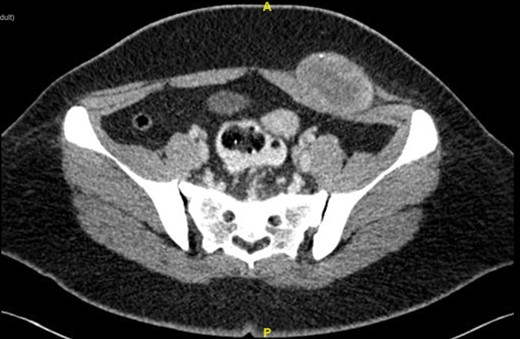

Computed tomography (CT) of abdomen showed well defined heterogenous enhancing soft tissue mass at left lower anterior abdominal wall measuring 6.04 × 3.91 × 6.09 cm3. There was presence of area of central necrosis within the lesion with punctate wall calcification. There was no fat component within. The mass has good plane of demarcation with the adjacent external and internal oblique muscle. Poor fat plane between the mass and left rectus abdominis and left transversus abdominis muscle likely due to compression (Fig. 1).

Computed tomography (CT) of abdomen showed well defined heterogenous enhancing soft tissue mass at left lower anterior abdominal wall. The mass has good plane of demarcation with the adjacent external and internal oblique muscle. Poor fat plane between the mass and left rectus abdominis and left transversus abdominis muscle.